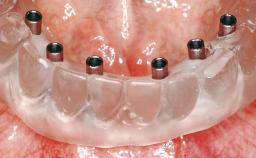

Immediate Loading of Six Implants in the Maxilla and Final Restoration with a Full-Arch CAD/CAM Zirconia FDP

# of Implants 6

Type of Implants One-Piece

Loading Protocol Immediate